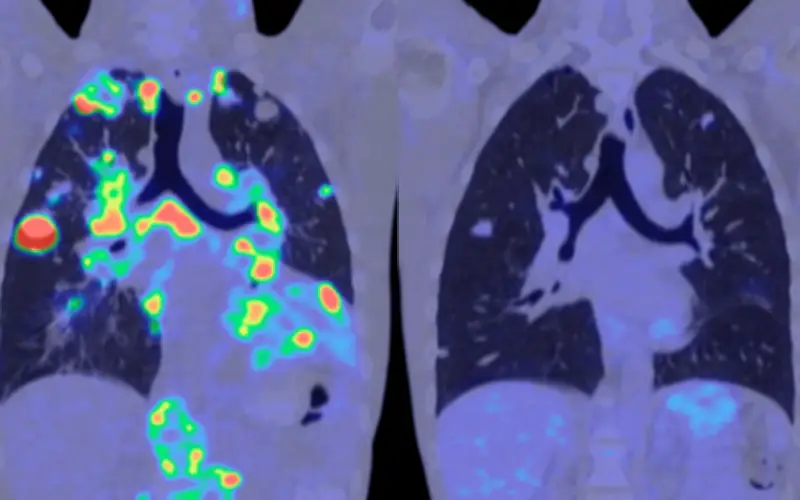

Más allá de la simple detección del cáncer, MethylScan demostró capacidad para identificar el tejido de origen de las señales cancerosas. Los patrones de metilación permitieron determinar qué órganos específicos estaban experimentando estrés o daño, incluso sin conocimiento previo de la enfermedad.

Los autores describen esta capacidad como un "radar de salud para el cuerpo" que podría revolucionar el monitoreo médico preventivo. "Es un avance emocionante que nos acerca al sueño de lograr un único análisis de sangre para la detección universal de enfermedades", concluyen los investigadores.